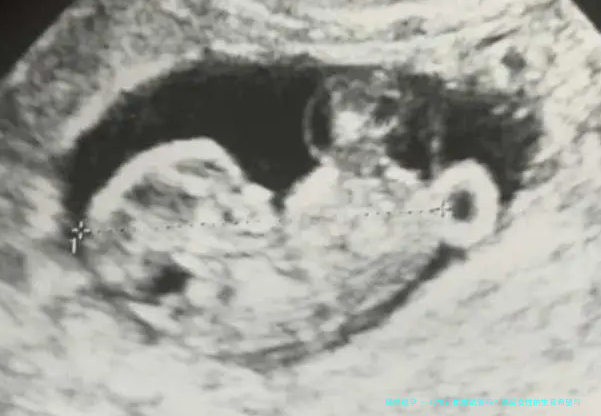

首先,简单科普下试管婴儿(IVF)是啥。简单说,就是把卵子和精子在实验室里“撮合”成胚胎,再移植回子宫。听起来高科技吧?但年龄在这儿扮演着大反派。为啥?因为女性卵巢功能会随年龄下滑,卵子质量和数量都大打折扣。生物学上,35岁后生育力就断崖式下降,到了42岁,卵子异常率可能高达80%以上。就像我朋友小张说的:“年轻时没当回事,现在想生娃才发现身体不等人。” 这不是吓唬你,而是提醒我们,技术虽强,但自然规律难违。

结合2020-2023年的全球研究,咱们用数据说话。国际生殖医学学会的报告显示,42岁女性做试管婴儿的活产率(成功生下健康宝宝的概率)平均只有10%-15%,远低于30岁女性的40%-50%。更扎心的是,中国辅助生殖数据中心2022年统计,42岁组的流产率飙到30%以上,而并发症如妊娠高血压的风险也翻倍。不过,别光看数字吓倒——技术进步带来了曙光。比如,新一代基因筛查技术(PGT)让42岁女性的成功率在个别案例中提升到20%。专家王医生告诉我:“数据是冷冰冰的,但个体差异大,有人42岁一次成功,有人35岁却屡败。” 所以,关键是要结合自身健康评估。